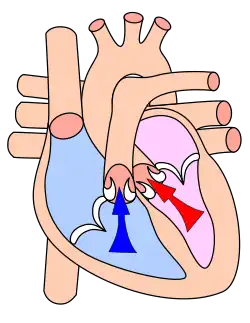

Systole

The heart in the systole phase. Systole, or contraction, of the heart is initiated by the electrical cells of the sinoatrial node, which is the heart's natural pacemaker. These cells are activated spontaneously by depolarization of their membranes beyond a certain threshold for excitation. At this point, voltage-gated calcium channels on the cell membrane open and allow calcium ions to pass through, into the main, or interior, of the muscle cell. Some calcium ions bind to receptors on the sarcoplasmic reticulum causing an influx of calcium ions into the sarcoplasm. The calcium ions bind to the troponin, causing a conformation change, breaking the bond between the protein tropomyosin, to which the troponin is attached, and the myosin binding sites. This allows the myosin heads to bind to the myosin binding sites on the actin protein filament and contraction results as the myosin heads draw the actin filaments along, are bound by ATP, causing them to release the actin, and return to their original position, breaking down the ATP into ADP and a phosphate group. The action potential spreads via the passage of sodium ions through the gap junctions that connect the sarcoplasm of adjacent myocardial cells. Norepinephrine (noradrenaline) is released by the terminal boutons of depolarized sympathetic fibers, at the sinoatrial and atrioventricular nodes. Norepinephrine diffuses across the synaptic cleft binds to the β1-adrenoreceptors – G-protein linked receptors, consisting of seven transmembrane domains – shifting their equilibrium towards the active state. The receptor changes its conformation and mechanically activates the G-protein which is released. The G-protein is involved in the production of adenosine 3',5'-cyclic monophosphate (cAMP) from adenosine triphosphate (ATP) and this in turn activates the protein kinase (β-adrenoreceptor kinase). β-adrenoreceptor kinase phosphorylates the calcium ion channels in the sarcolemma, so that calcium ion influx is increased when they are activated by the appropriate transmembrane voltage. This will of course, cause more of the calcium receptors in the sarcoplasmic reticulum to be activated, creating a larger flow of calcium ions into the sarcoplasm. More troponin will be bound and more myosin binding sites cleared [of tropomyosin] so that more myosin heads can be recruited for the contraction and a greater force and speed of contraction results. [Phosphodiesterase catalyses the decomposition of cAMP to AMP so that it is no longer able to activate the protein kinase. AMP will of course, go on to be phosphorylated to ATP and may be recycled.] Noradrenaline also affects the atrioventricular node, reducing the delay before continuing conduction of the action potential via the bundle of HIS.